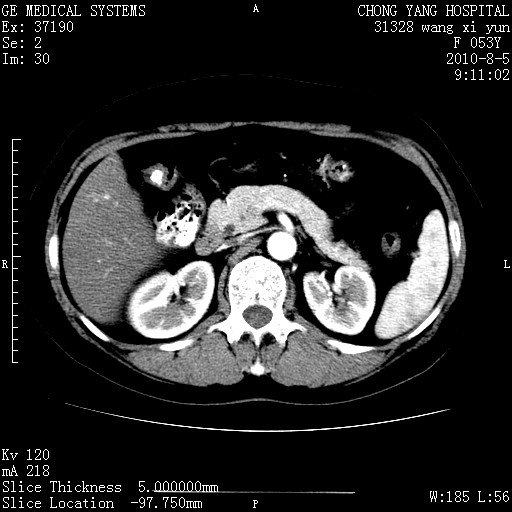

标题: CT28214:F41Y 血尿二十天,建议盆腔平扫加增强。

胆管细胞ca?

1)考虑肝左叶胆管细胞癌。2)脂肪肝。

支持胆管细胞ca。